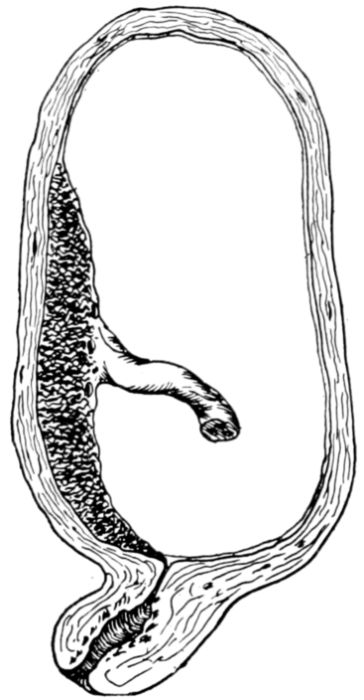

| 20. | Diagram of developing fetus, cord, membranes and placenta in utero | 69 |

| 25. | Embryo about 5.5 cm. long in amniotic sac | 77 |

| 26. | Outlines of fetus at different stages | 78 |

| 27. | Full term fetus in utero | 81 |